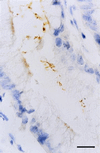

In vitro or animal models have been used to investigate the pathogenesis of Helicobacter pylori infection. However, extrapolation to humans of results obtained with these heterologous models remains difficult. We have developed a new model for the study of H. pylori infection that uses human entire embryonic stomachs engrafted in nude mice. At 80 days after implantation, 22 of these xenografts, which exhibited a mature gastric epithelium, were inoculated with 10(7) to 10(8) CFU of either H. pylori LB1, a freshly isolated H. pylori strain (n = 12), or H. pylori ATCC 49503 (n = 10). After 12-week examination, H. pylori LB1 persistently colonized the antrum of all inoculated grafts, as assessed by culture (mucus and mucosa), immunohistochemistry (mucosa), and a rapid urease test (mucus). H. pylori ATCC 49503, either before or after in vivo passage, permitted only a transient 2-week colonization in one of the five inoculated grafts in both groups. Colonization was always associated with an increase of gastric juice pH. A mild neutrophil infiltration of the gastric mucosa was noted solely in infected grafts. Transmission electron microscopy showed adherence of H. pylori organisms to epithelial cell surface. In six animals, intracytoplasmic location of this bacterium was observed in the antrum or the fundus. These results allow us to propose this model as a new ex vivo model for the study of specific H. pylori-gastric cell interactions.